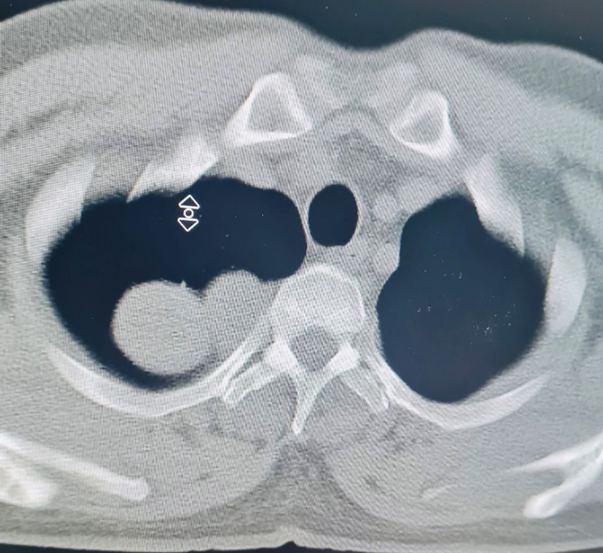

Qua chụp cộng hưởng từ và cắt lớp vi tính phát hiện bệnh nhân có khối u trong ống sống ngực đã phát triển vào lồng ngực với kích thước lớn 3×4 cm. Khối u này đã phát triển vào trung thất sau ăn sát hõm đỉnh lồng ngực, đè đẩy vào bó mạch thần kinh cánh tay, đặc biệt là tĩnh mạch dưới đòn trái.

Hình ảnh khối u của bệnh nhân Thiện trên phim chụp. Ảnh: Bệnh viện cung cấp